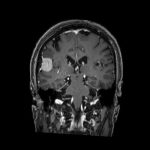

712

'25年12月

70代

下垂体腫瘍

頭蓋内腫瘍摘出術